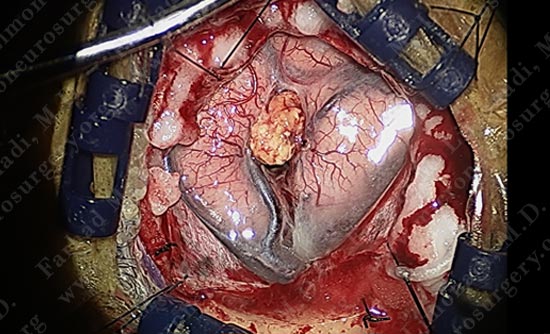

Tumor is removed without any injury to the motor cortex or adjacent neuro-vascular structures. Patient is awake and doing well with no neurological deficit.

Utilizing computer navigation, a small craniotomy was performed precisely over the tumor and the tumor was removed using this small opening.